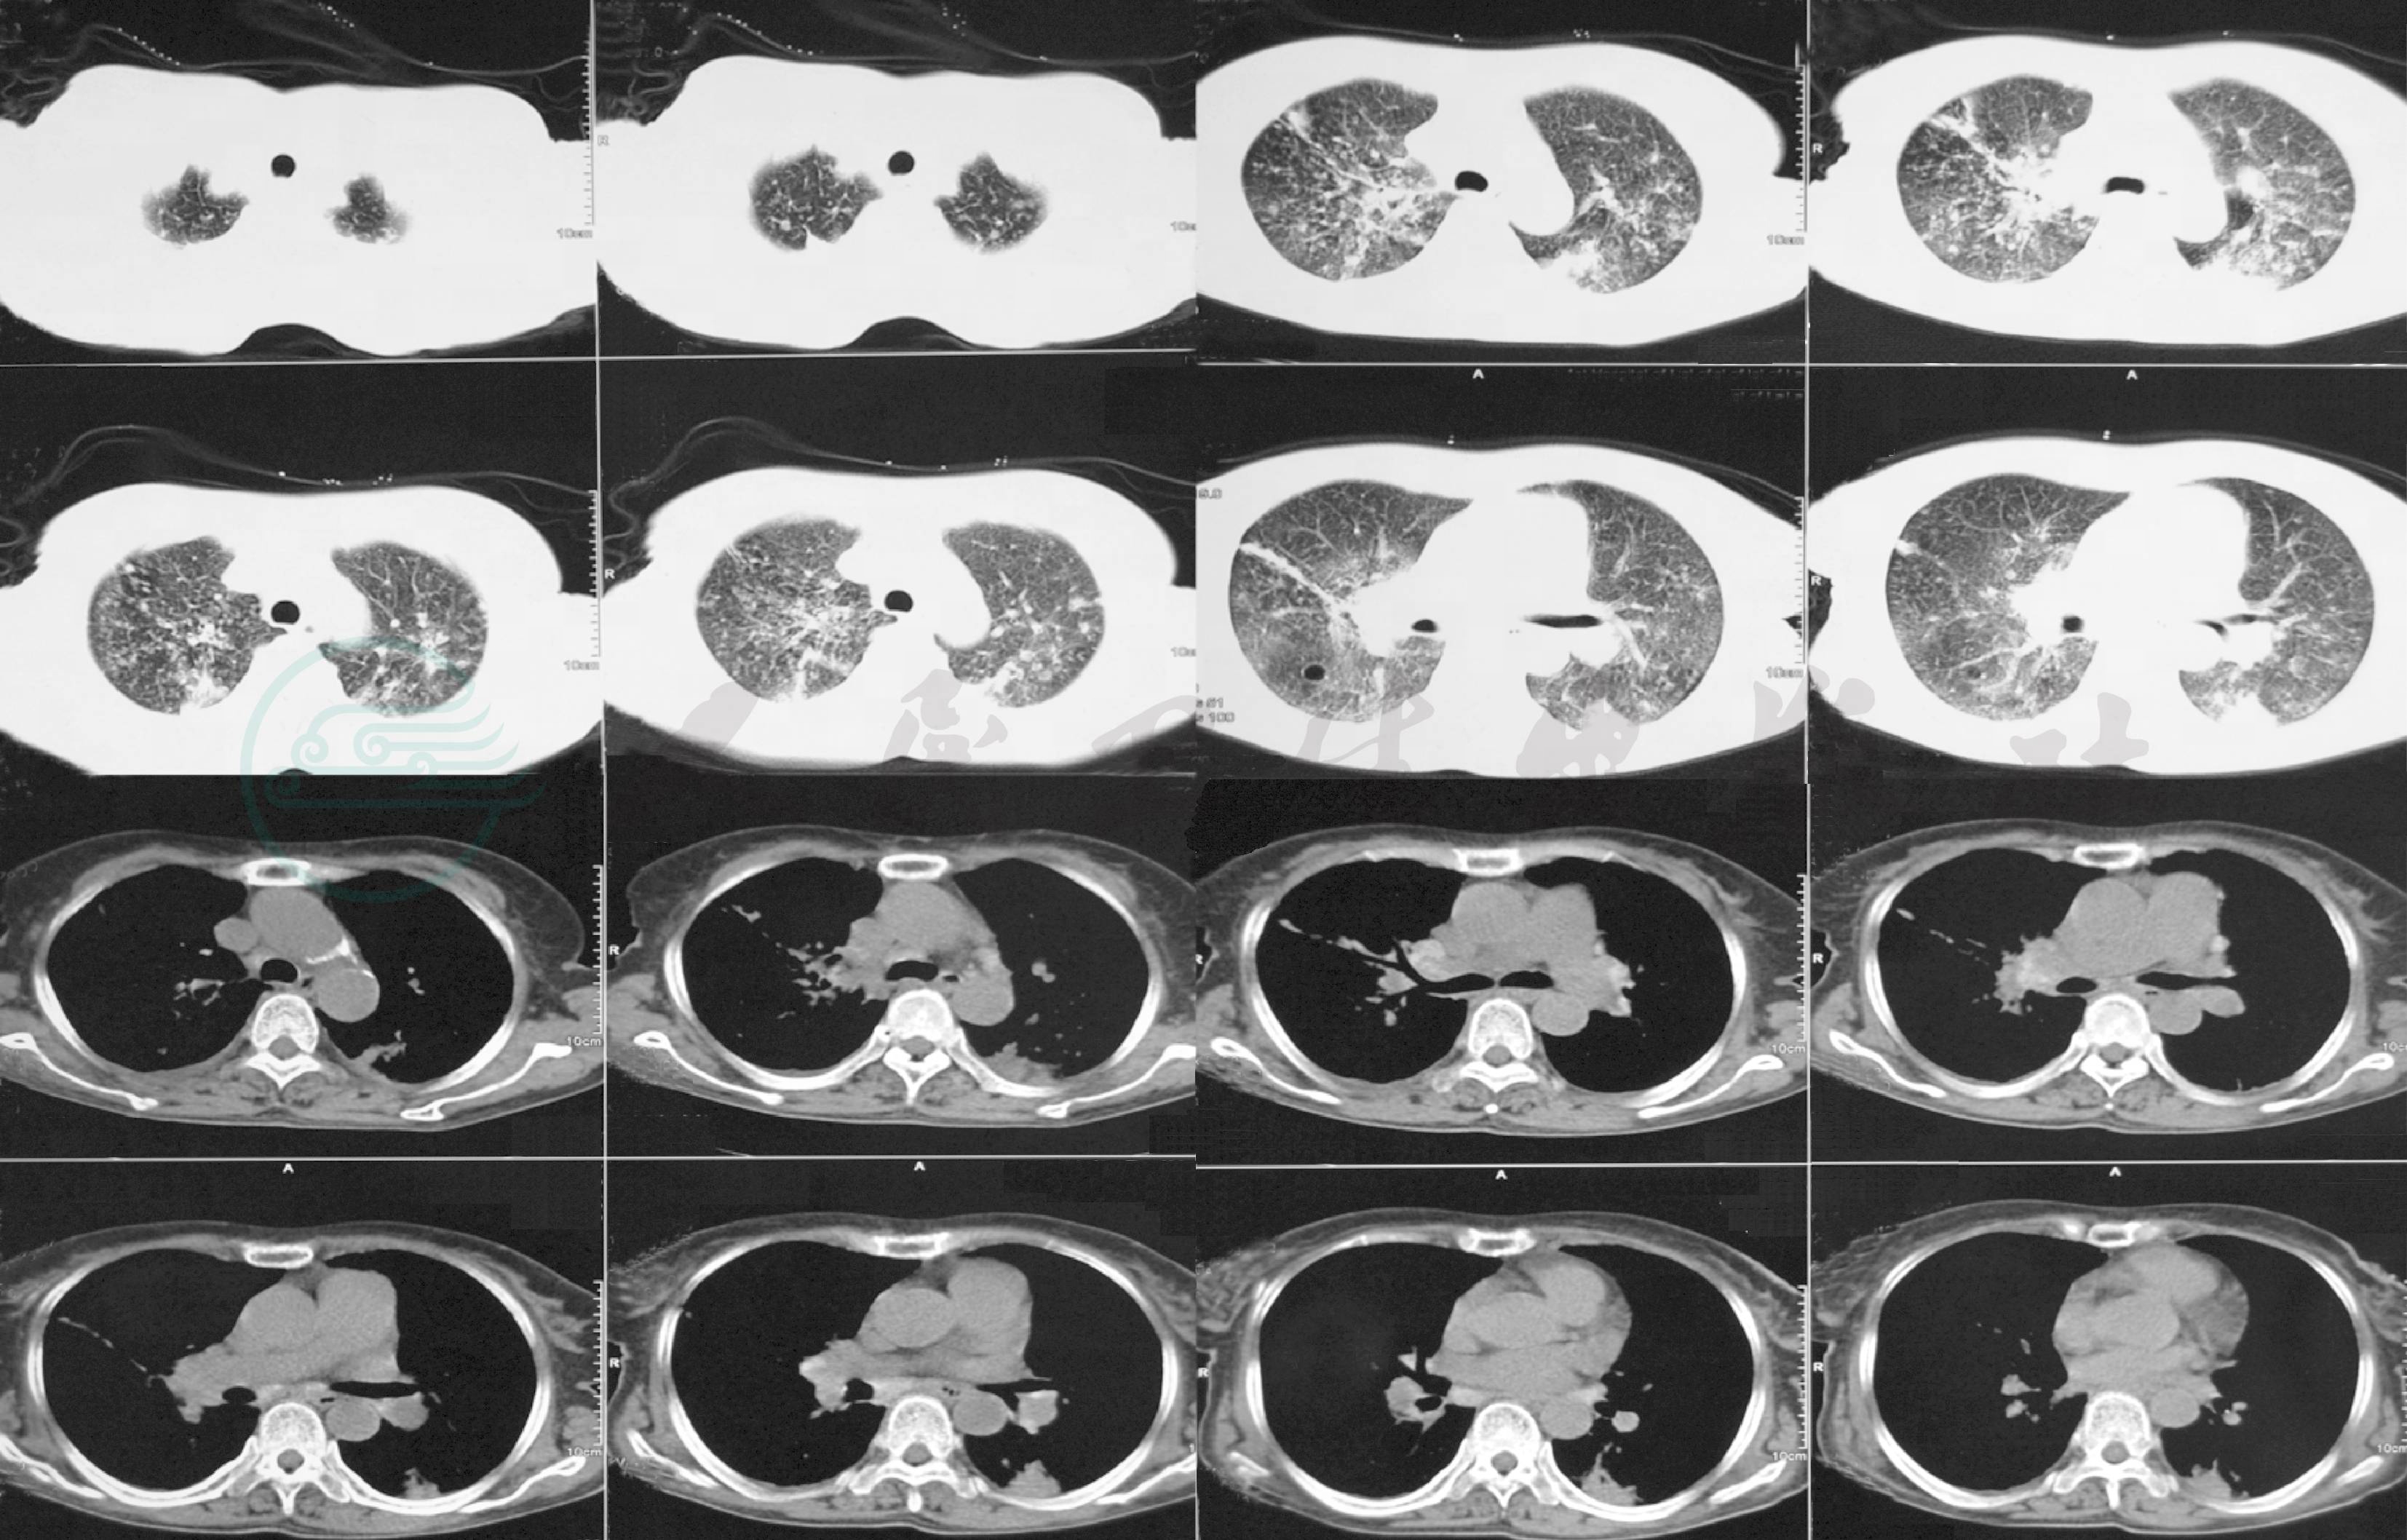

胸部CT:双肺多发斑片、结节影,以双肺上叶及下叶背段为主,多考虑肺结核;纵隔及肺门多发淋巴结肿大,部分钙化;左侧胸腔积液,双侧胸膜增厚(图1)。

图1 胸部CT

双肺多发斑片及结节影、纵隔及肺门淋巴结肿大,部分钙化